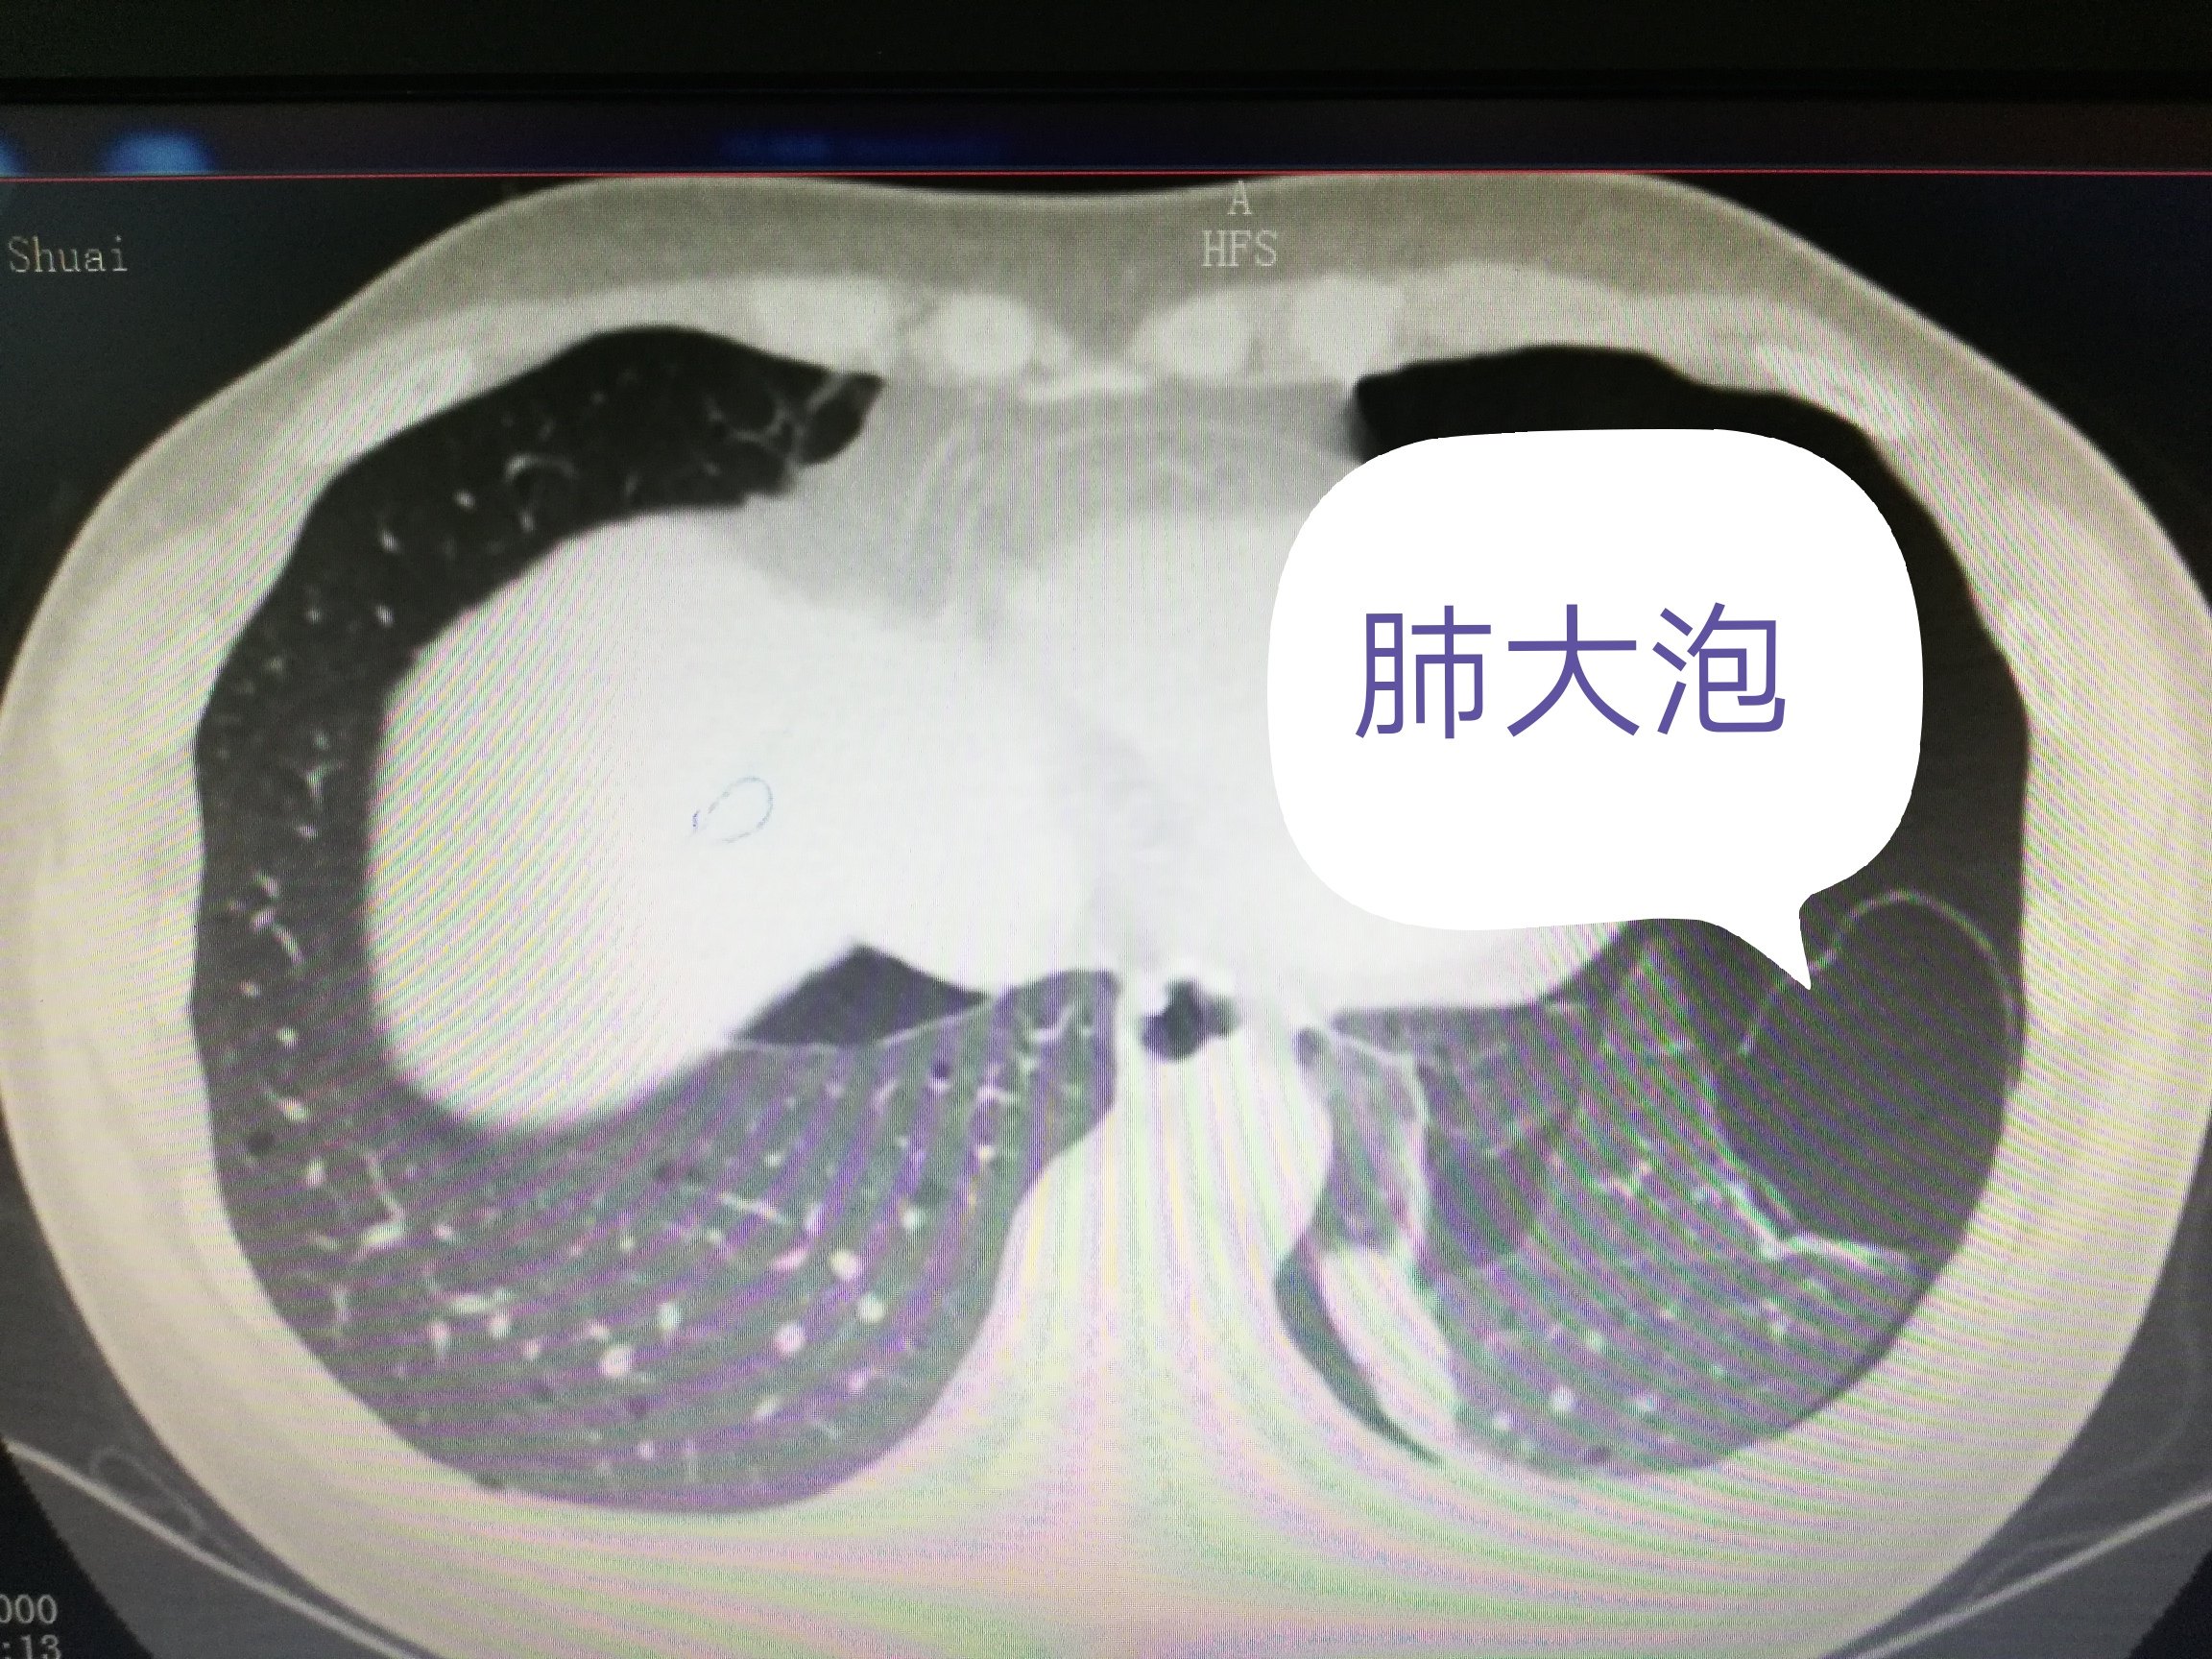

肺大泡的诊断与治疗 肺大疱

肺大泡的症状有哪些 应该如何治疗 每日头条

肺大泡的症状有哪些 应该如何治疗 腾讯新闻

肺大泡的症状有哪些 应该如何治疗 医生一文给你讲清楚

肺大泡的症状有哪些 手术能治好肺大泡吗 到底该如何治疗 雪花新闻